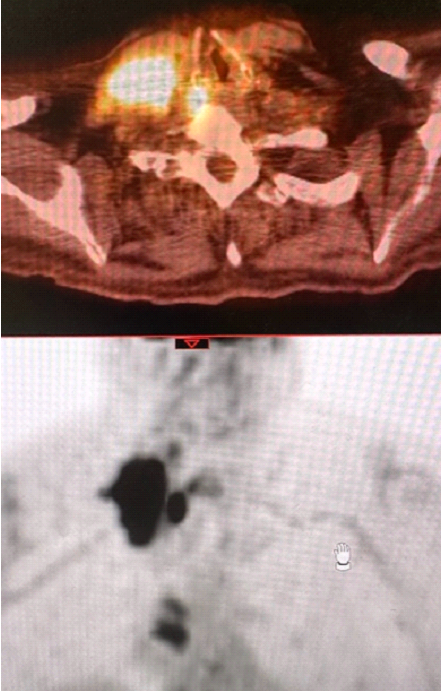

78 yo man with significant comorbidites (vasculopath, DMII with left BKA, cad, worsening dementia) has a distant history 15 years ago of treatment for dlbcl in remission now found to have growing supraclav node biopsied positive for nodular sclerosing Hodgkin's Lymphoma. Very poor chemo candidate per med onc. Asking if we can give RT alone. PET shows right cervical/supraclav nodal conglomerate and a Right IMN. What would you do here, has anyone done STLI? Just treat involved field and follow?

• petHL.png

petHL.png

643.4 KB · Views: 169